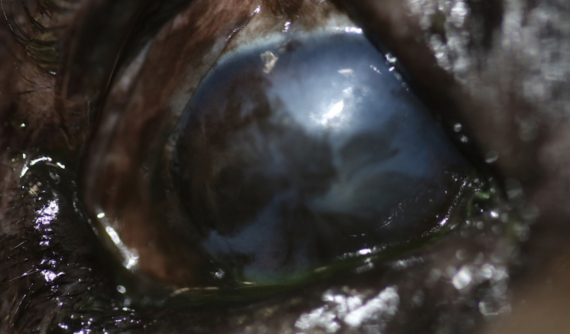

En el caso de Brutus, tras la cirugía de queratectomia aplicamos la crioterapia. La herida ha cicatrizado muy bien y por ahora no hay ningún signo de recidiva.

Gracias a este procedimiento, Brutus ha recuperado la mayor parte de su visión en este ojo .

Brutus varios meses tras la intervención, muy contento! Fotos: IVO.